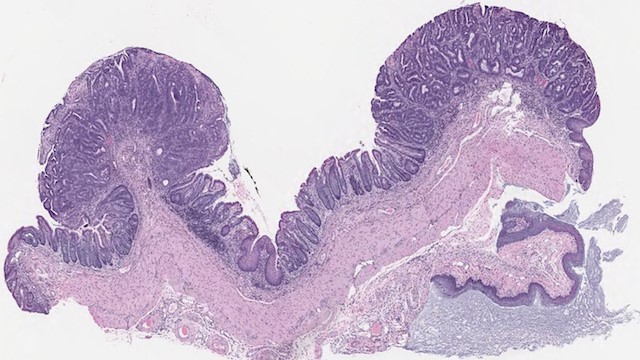

近年来,科学家已经研发类器官---培养皿中的干细胞来源器官,用于许多组织,包括肾脏,肠道和脑。虽然这些微型器官提供一个有用的工具来研究发育和疾病,许多科学家仍然认为动物模型需要用于验证这些体外研究。2017年5月1日两个连续的研究发发表在《自然生物技术》杂志,科学家结合这两种方法通过移植类器官到小鼠体内,形成一种更快,更准确的结直肠癌(CRC)小鼠模型。 结直肠癌(CRC)在美国是最常见的癌症之一,是国家癌症相关死亡的第二大原因。国内结直肠癌等发病上升迅速且出现年轻化趋势。尽管治疗这种疾病需要更好的治疗,转基因动物模型的CRC仍然相当有限。 “因为不是众所周知小鼠癌症发生在小肠,而不是大肠,这正是人类癌症发生地”,Scott Lowe,这项研究的共同作者之一,纽约纪念斯隆凯特林癌症中心的生物学家说。“它们得到这么多(肿瘤),生病并且需要在癌症扩散到一个与人类发生癌症类型相似的阶段前牺牲。” 2009年,Hans Clevers和其实验室的博士后Toshiro Sato用来源于小鼠肠道的成体干细胞培育出首个微型肠道(mini-guts)类器官,近年来,研究人员试图改进这些使用微型肠道的动物模型。这项研究的共同作者之一,康奈尔大学生物化学教授Lukas Dow说:“Clevers和他的同事一旦确定培养条件,他们便证明了遗传操作能力,打开任何人想要使用这些系统的领域”。 类器官中包含多种已分化的细胞类型,这些细胞类型在体内相应的器官中也有存在。比如,小肠上皮的所有细胞类型在Sato等报道的小肠类器官模型中均有体现。介导类器官形成的信号通路与体内器官发育与稳态维持的信号通路是相同的,因此,细胞因子、生长因子和小分子也要添加到培养基中,以激活或者抑制参与类器官形成的特定信号通路。制备不同的类器官需使用不同的添加物组合,即使对于小肠和结肠等结构非常相近的组织,添加物的组合也不尽相同。